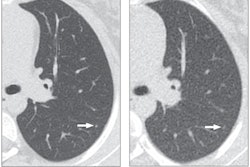

One likely explanation for the variability in CT radiation dose is the application of iterative reconstruction to the CT scans at hospital B, the researchers noted. In this study, the effect of iterative reconstruction stood out when a shift in trauma head CT protocol parameters was implemented at hospital B halfway through the evaluation period. The iterative reconstruction setting was elevated from "standard" to "strong," which led to no less than a 35.5% drop in average CTDIvol.